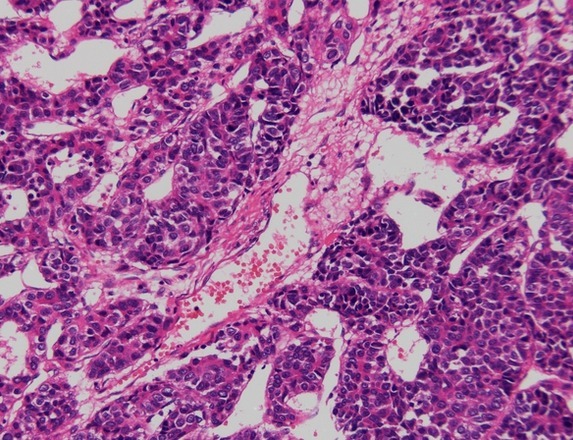

苏木精 — 伊红染色法 ( hematoxylin-eosin staining ) ,简称HE染色法 ,石蜡切片技术里常用的染色法之一 。苏木精染液为碱性 ,主要使细胞核内的染色质与胞质内的核糖体着紫蓝色 ;伊红为酸性染料 ,主要使细胞质和细胞外基质中的成分着红色 。HE染色法是组织学、胚胎学、病理学教学与科研中基本、使用广泛的技术方法。

染色结果:细胞核蓝色,细胞质红色。

文献和实验相关专题 本篇文章主要介绍了采用苏木素(Hematoxylin)-伊红(Eosin)染色法对细胞染色的实验原理、实验用品和具体实验步骤。 HE染色法 一、原理 苏木素(Hematoxylin)-伊红(Eosin)染色法,简称HE染色法。 HE染色法采用两种染料即碱性染料苏木素和酸性染料伊红分别于细胞核 和细胞质发生作用,使细胞的微细结构通过颜色而改变它的折光率,从而在光镜下能清晰地呈现出细胞图像。该染色过程既有化学